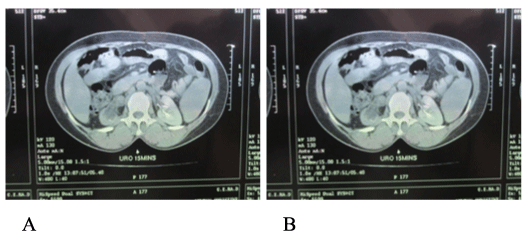

Kidney function tests showed hypercreatinemia (creatinine 13.46g/l –normal range is 6-12g/l, BUN 0.37g/l), and a complete blood count revealed a hypochromic microcytic anemia with a hemoglobin of 9.5g/dl. Urine culture was sterile. On cystoscopy, there was no bladder tumour except for active bleeding observed from the right ureteral orifice. Diagnostic ureterorenoscopy could not be performed. Urine cytology revealed fresh red blood cells with masses of atypical urothelial cells suggestive of urothelial carcinoma but the localization was inconclusive, neither could the tumour be graded. A right radical nephroureterectomy was performed via a two incisions (Figure 2). The specimen "en bloc" (Figure 3) was sent for pathological analysis. The patient is reporting well one year post-operation.

Figure 2: In situ dissection showing the inferior vena cava, right renal vein

(on right angle clamp), and ureter (on vessel loop) during nephrouretectomy